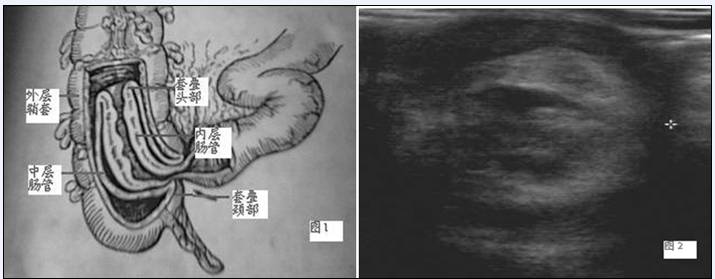

肠套叠是指部分肠管及其系膜套入相邻近的肠腔内,多为顺行性,即近端肠管套入远端肠腔内。

婴幼儿肠套叠在临床上常表现为患儿阵发性腹痛、哭闹不安、呕吐及果酱样便,部分患儿可触及腊肠样包块。有时单纯靠临床表现作出诊断很难。超声检查可以弥补临床诊断之不足。由于小儿腹壁较薄,高频探头扫查腹部时,于横切面上肠套叠包块呈 “同心圆”征象,于纵切面上呈“套筒”征象,具有特征性表现。彩色多普勒血流显像可反映套入肠腔部分的血液循环状态,为临床选择不同的治疗方案提供依据。